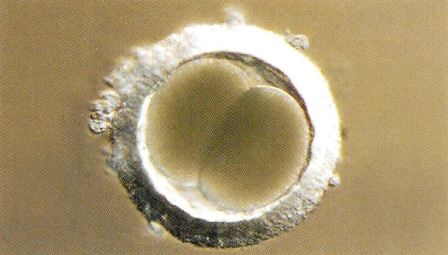

Die Befruchtung, die Vereinigung einer Samenzelle mit einer Eizelle, findet weit oben in der Gebärmutter, in den Eileitern statt. Am Ende der folgenden Woche wandern die Embryonen von dort in Richtung der Gebärmutterhörner. Sie schwimmen in der Gebärmutterflüssigkeit, bewegen sich darin fort und können sogar von einem Horn in das andere wandern. So ist es möglich, dass die Befruchtung im rechten Eileiter stattgefunden hat, und die nachfolgende Einnistung im linken Gebärmutterhorn. Schliesslich werden die Embryonen im Bereich einer Gebärmutterdrüse unbeweglich. Diese Einnistung des Embryos in der Gebärmutterschleimhaut findet relativ spät, etwa um den 16. Tag der Trächtigkeit statt. Erst ab diesem Zeitpunkt beginnt die Entwicklung der Embryonen und ihrer Embryonalhüllen.

Die Trächtigkeit beginnt mit der Vereinigung von Samenzelle und Eizelle, der unmittelbar die ersten Zellteilungen folgen.